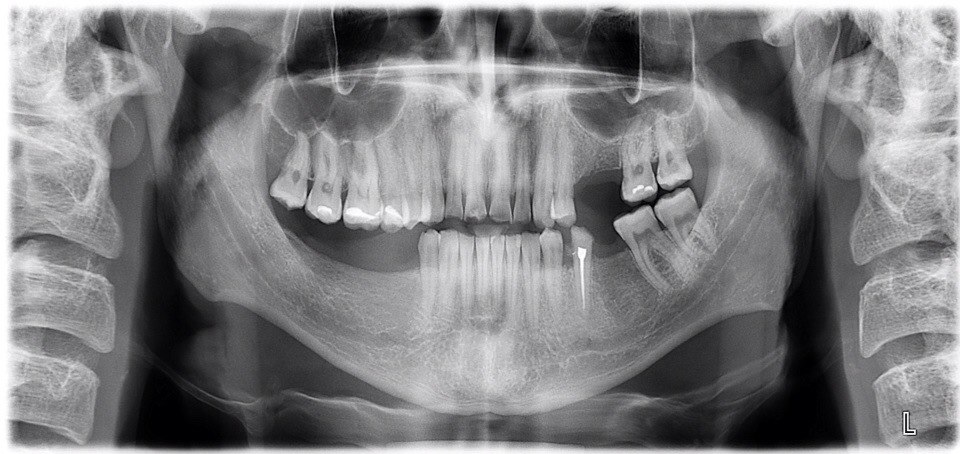

Что можно сделать с моей челюстью? Предлагают обточить верхние зубы под коронки 14, 13, 12, 11, 21, 22, 23, 24, 27 и установить мост, чтобы поднять прикус, т.к. зубы сильно сточились. На нижней челюсти обточить 34 и 45 одеть коронки + отсутствующие зубы заменить частично-съемным протезом, при этом депульпировать и сточить 18 и 17 зуб, так как они опустились до нижней челюсти и мешают установке съемного протеза. Можно ли как-то восстановить верхние зубы, чтобы не депульпировать их и не одевать коронки?